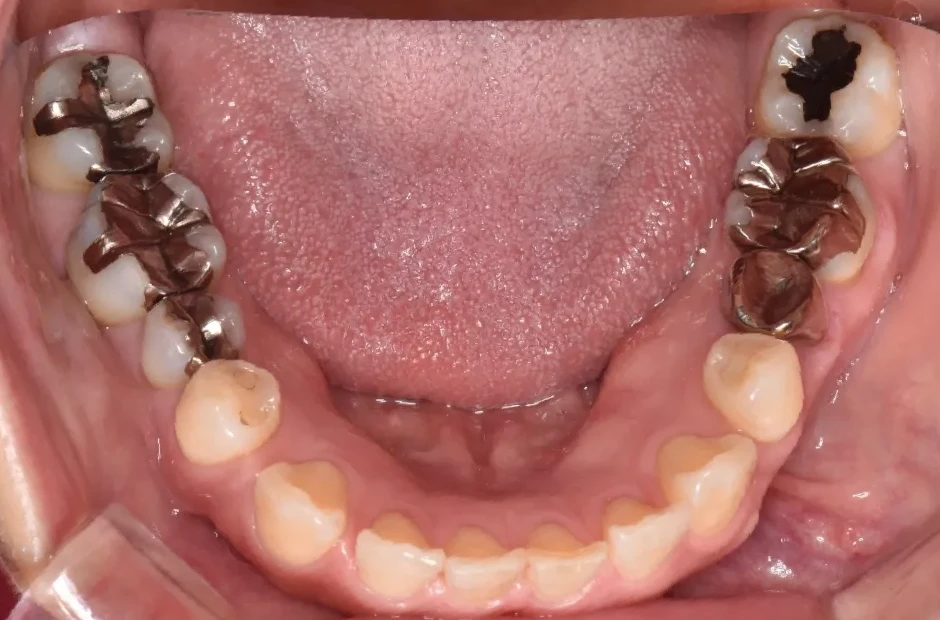

叢生

| 診断名・主訴 | 叢生 |

|---|---|

| 年齢・性別 | 43歳・女性 |

| 治療期間・回数 | 2年7か月 27回 |

| 治療に用いた主な装置 | 舌側矯正 |

| 抜歯部位 | 両顎4,4 |

| 治療費 | 100万円(税抜) |

| リスク・副作用 | 装置による違和感・疼痛・歯肉退縮・歯根吸収・虫歯のリスクなど |

治療前